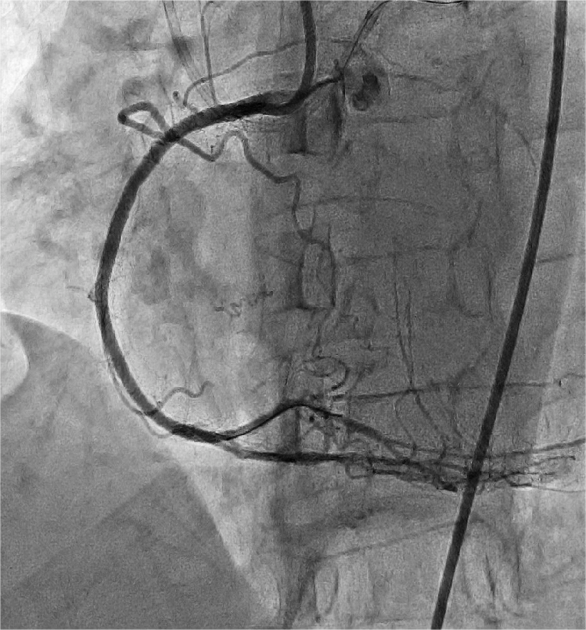

4月24日,朱舜明副主任医师为患者制定周密的手术方案和风险处理方案,朱舜明副主任医师、唐治国主治医师、张翔主治医师、张豪住院医师开展持续3小时的介入手术。术中穿刺桡动脉和股动脉,双路径同时造影显示病变血管完整结构,开展Reverse-CART技术,将逆向导丝送入正向指引导管,跟进微导管,交换导丝后用球囊扩张病变,沿逆向导丝送入双腔微导管至闭塞血管远端,沿双腔微导管送入正向工作导丝至右冠后降支,并退出逆向微导管和导丝,采用血管内超声精细评估病变情况,最终向右冠状动脉内植入3枚支架。术后多体位造影未见残余狭窄及贴壁不良,完美结束手术。

图3 交换RG3导丝沿逆行血管路径通过病变部位